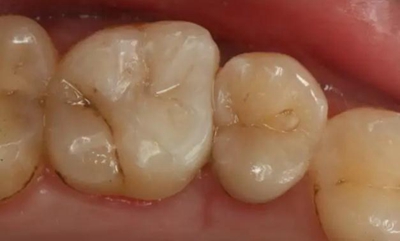

病例一 女性,20歲,大學生,要求補牙,檢查口內(nèi)可見A6大面積缺損,近中牙齦息肉,拍X片,根管充填物略差,但根周未見明顯陰影,口內(nèi)檢查無叩痛。建議患者冠延長手術+高嵌體修復。

患牙遠中邊緣嵴完整,強度沒有降低,故擬保留遠中邊緣嵴,高嵌體修復。首先去除腐質(zhì)及原墊底材料,流體樹脂+3M Z350XT樹脂墊底。局麻下行冠延長手術。在此需要提及個人的一個觀點。冠延長手術原則上要求3-6個月以上才能永久修復。但是個人喜歡后牙肩臺建立在齦上,所以修復后的修復體邊緣位于牙齦上方1mm,對牙周的愈合影響較?。ㄈ绻麨辇l下邊緣則要慎重),故該患者術中按照齦上邊緣的設計進行冠延長手術。以下為術中: